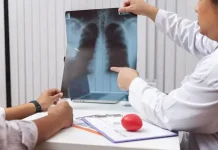

Sulsel Maksimalkan Portable X-Ray Percepat Deteksi TBC

- Kesehatan

- By Sunarti Tasik Malilin

- 20 Jan 2026